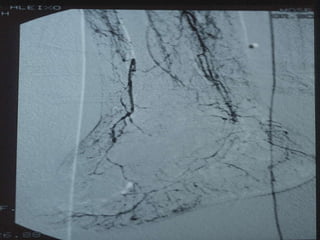

O PÉ DIABÉTICO E SUAS ESPECIFICIDADES   VASCULOPATIA DIABÉTICA   ALTERAÇÕES DA MICROCIRCULAÇÃO CUTÂNEA ATEROSCLEROSE DAS EXTREMIDADES INFERIORES  (calcificações parietais e predomínio de doença femoro popliteia e distal) FUNÇÃO IMUNE CITOMEDIADA ESTÁ ALTERADA  -  MAIOR RISCO DE COLONIZAÇÃO E INFECÇÃO BACTERIANA

ISQUÉMIA CRÍTICA TRATAMENTO - Revascularização Cirurgia convencional Cirurgia endovascular - Proximal - Distal - Multisegmentar

O PÉ DIABÉTICOE SUAS ESPECIFICIDADES VASCULOPATIA DIABÉTICA ALTERAÇÕES DA MICROCIRCULAÇÃO CUTÂNEA ATEROSCLEROSE DAS EXTREMIDADES INFERIORES (calcificações parietais e predomínio de doença femoro popliteia e distal) FUNÇÃO IMUNE CITOMEDIADA ESTÁ ALTERADA - MAIOR RISCO DE COLONIZAÇÃO E INFECÇÃO BACTERIANA

ISQUÉMIA CRÍTICA TRATAMENTO- Revascularização Cirurgia convencional Cirurgia endovascular - Proximal - Distal - Multisegmentar